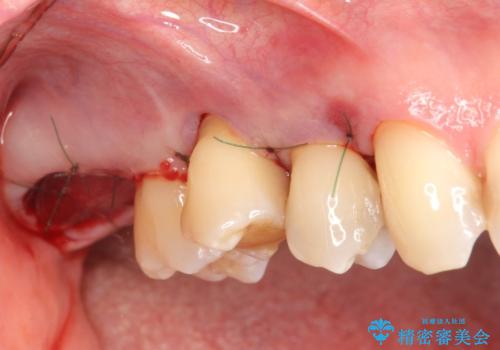

部分矯正を含む 歯周病治療 (再生治療・歯周ポケット除去・MTM・連結補綴)

検査の結果、強い歯ぎしりによる歯の周囲の骨の吸収が認められたため歯槽骨の再生・歯周ポケットの除去・力に対抗する連結補綴・補綴前処置としての小矯正を計画します。

今回連結補綴を行うにあたり、歯周病の問題を解決するために再生療法・歯周ポケット除去手術を、またより歯の神経を保存し力に対抗できる環境を整えるために小矯正を行い精度の高いメタルボンドクラウンを製作することができました。